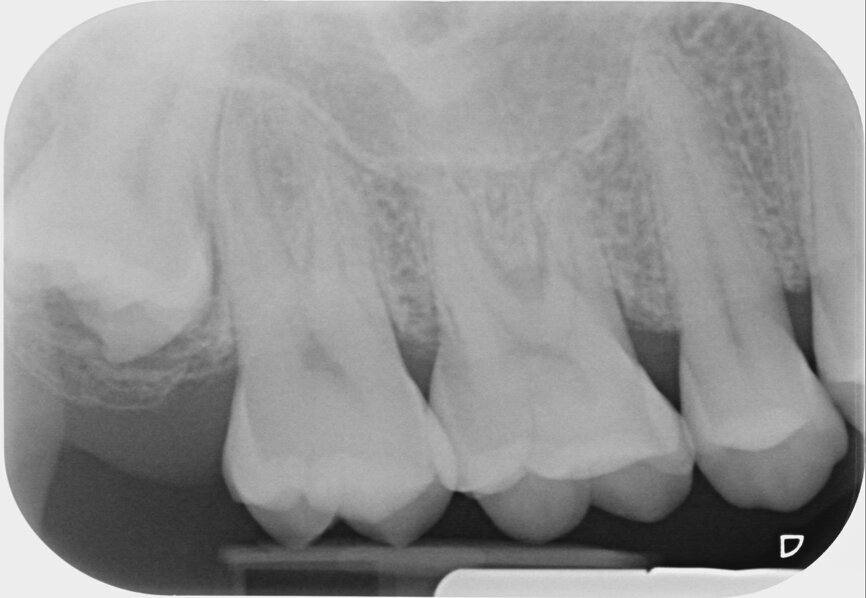

She had been stressed and grinding. More deliberation, still no further was the diagnosis. The tooth was dressed once again, with a change in the medicament. Still no joy. A restorative dentist then proceeded to drill the crack out and restore with composite. Still no joy. The tooth was taken out of occlusion when one dentist noticed the development of periodontal ligament widening on one of the long-cone periapical radiographs. The root canal treatment was completed jointly by two excellent endodontists and the second mesiobuccal canal was located. Under any other circumstances, it was a fantastic clinical outcome. Unfortunately, the pain was unabating (Fig. 2). Let us see as much as we can. A CBCT scan was taken that was also inconclusive (Fig. 3). Was it something to do with the sinus? The radiographic report was suggestive, but again nothing conclusive. Towards the end of the two weeks, the patient marched herself into the office of the exodontist to have the tooth extracted. Misery. We had failed.